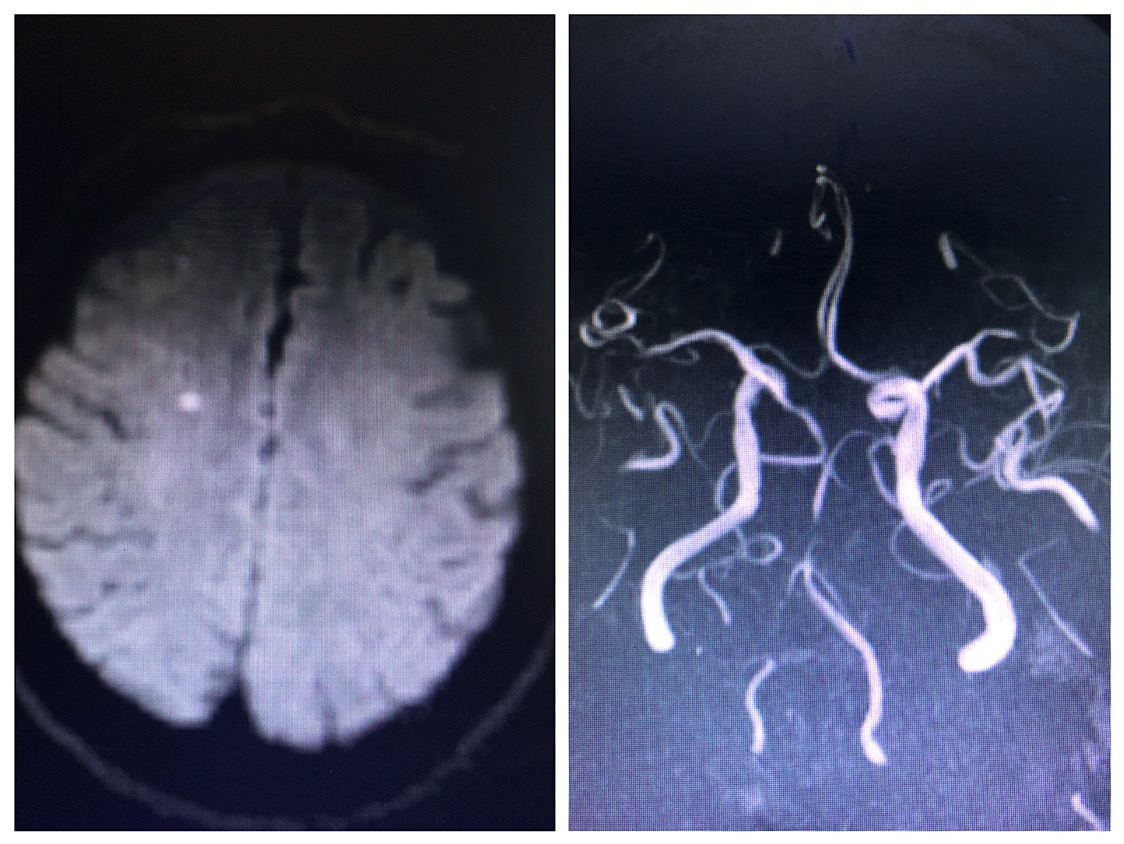

头CT示左侧小脑半球,右侧半卵圆中心及双侧基底节多发腔隙性脑梗死。

核磁示:右侧半卵圆中心新发腔隙性脑梗死,颅内多支血管狭窄,双侧胚胎型大脑后动脉。